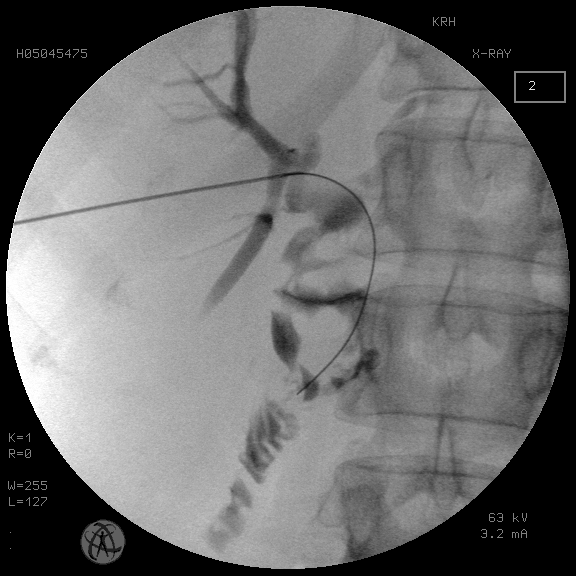

Также интересным представляется отсутствие полной стриктуры БДА на фоне холелитиаза. Механическая желтуха в этом случае обусловлена не полной рубцовой непроходимостью анастомоза, а персистирующим в этой зоне конкрементом, что позволяет даже при множественном холелитиазе уже при первичной пункции внутрипеченочного желчного протока визуализировать зону БДА по сбросу контраста в петлю тонкой кишки или прохождение поискового проводника (рис. 8).

Рис. 8. Прохождение поискового проводника через зону БДА при первичной пункции желчных протоков

Fig. 8. Passage of the search guide through the BDA zone during primary puncture of the bile ducts

Поскольку стриктура БДА на фоне холелитиаза не носит полный характер, то ее антеградная баллонная дилатация не вызывает трудностей, в отличие от «чистой» бескаменной стриктуры, при которой с частотой до 25 % не удается пройти из желчного протока в отводящую петлю тонкой кишки.